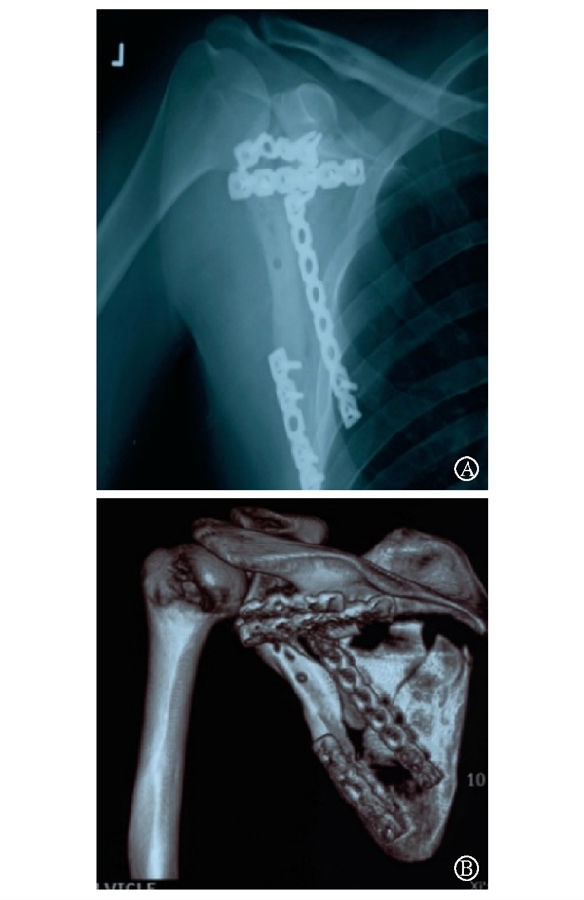

病例2为1例累及肩胛盂、肩胛颈和肩胛骨体部的复杂肩胛骨骨折(图11-12)。

术前设计采用跨骨折区域钢板螺钉固定(图13)。术中可见纵向骨折区域骨质薄弱,骨折粉碎严重,钢板放置位置有限,操作极其困难(图14)。术中采用多块接骨板跨骨折区域固定,术后X线片及三维CT重建显示复位满意(图15)。针对此病例,如果采用缝线辅助固定技术,可使手术操作过程简化,达到同样的固定效果(图16)。

图15 术后X线片及CT三维重建示骨折复位满意,内固定位置良好 图A:术后X线片;图B:术后CT三维重建